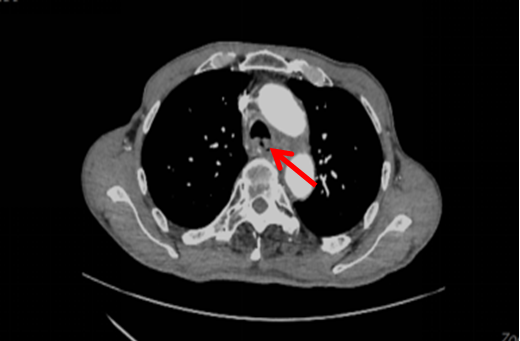

一名60岁男性患者,今年9月底因“咳嗽、咳痰10天”入住我院,1年前在外院确诊食管恶性肿瘤(中分化鳞癌),行放化疗,胸部增强CT显示:胸上段食管癌并食管-气管瘘,右肺及左肺下叶炎症(图1)。(2022-09-26)支气管镜(图2):距离隆突约3.0cm处可见一类圆形瘘口,有黄脓痰粘附,予吸净分泌物后见瘘口处粘膜充血、水肿、溃烂,直径约4mm,4.2 mm外径的电子支气管镜不能通过。(2022-10-17)支气管镜(图3)显示瘘口周围有新生物,活检病理证实为鳞癌。

图1:胸部CT(箭头指向为食管气管瘘口)